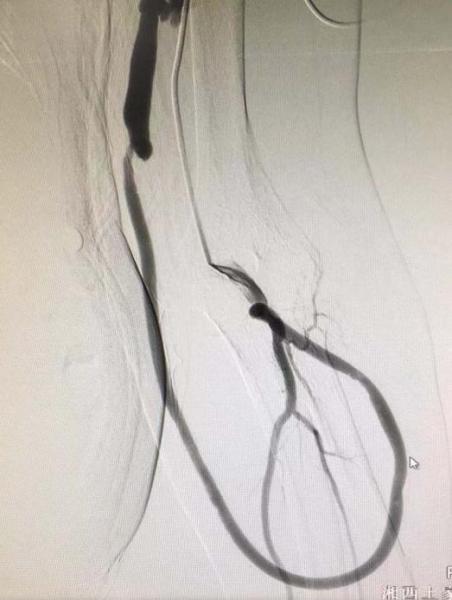

患者路某某,因尿毒症规律透析治疗多年,于1年前行人工血管动静脉瘘成形术,长期以人工血管行透析治疗,近日,因发现人工血管震颤减弱来我院介入血管科就诊。

术前B超检查提示:左上肢贵要静脉、环形人工移植血管环内实质性低回声。介入血管科副主任丁文金经综合评估,反复研究讨论,并与患者及家属充分沟通后,结合患者目前情况,决定采用介入接触性溶栓、血管球囊扩张成形的手术方式开通血管通路。

术中由丁文金主刀,带领介入血管科团队顺利为患者进行了接触性导管溶栓及狭窄段血管PTA球囊扩张成形术,术后持续行接触性溶栓治疗,再次复查造影提示动静脉瘘通畅性良好,术后患者动静脉瘘震颤恢复良好,后期行人工血管透析血流量良好治疗顺利,患者病情恢复良好出院。